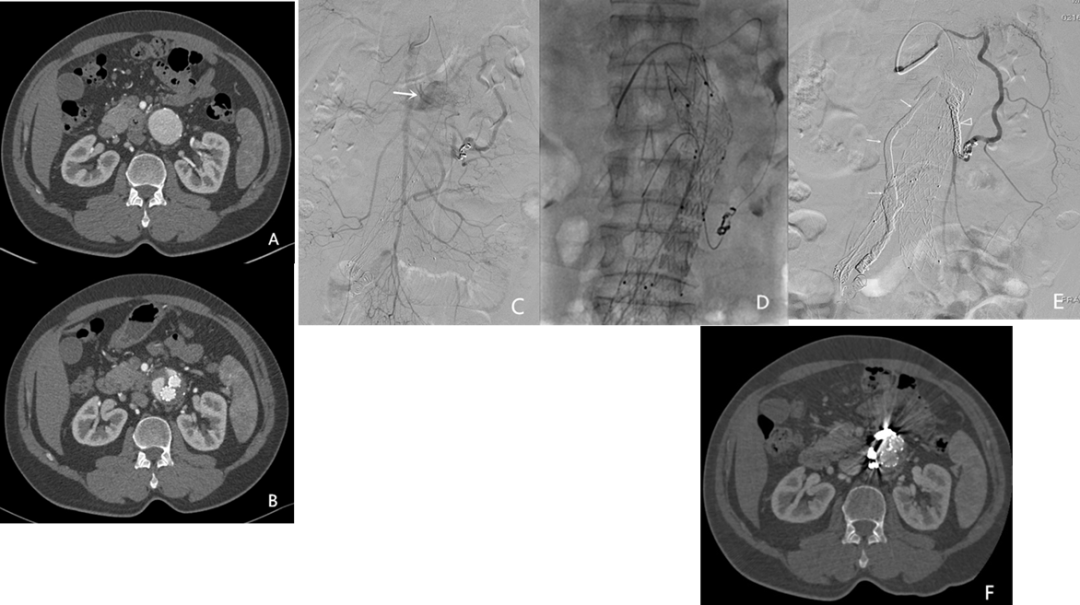

一例术前发现双侧腰动脉,因当时认为“不粗”未处理。术后 CTA 显示 II 型内漏伴瘤体增大。最终经髂内动脉入路,先以弹簧圈构建支架,再注入医用胶封闭瘤囊,成功止漏。

其他补救方法还包括:

经皮直接穿刺瘤囊注射胶;

腹腔镜下结扎返流血管。